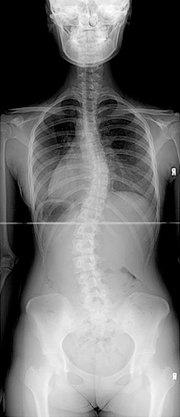

보조기 착용전

보조기 착용 후 교정된 모습